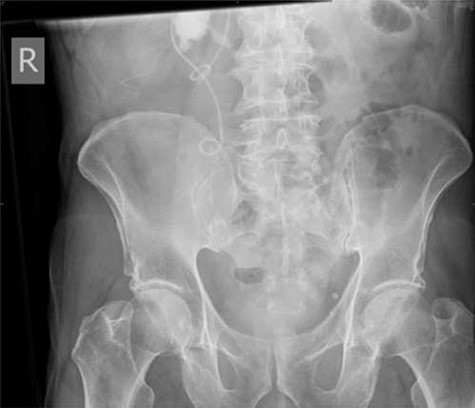

Following completion of chemotherapy, 12 weeks after stent insertion, the patient attended clinic for stent removal however, the stent could not be visualized on flexible cystoscopy. An abdominal X-ray showed proximal migration of the stent with the proximal end of the stent appearing to wrap around the aforementioned staghorn calculus (Fig. 4).

Plain abdominal X-ray performed at follow-up demonstrating proximal ureteric stent migration.